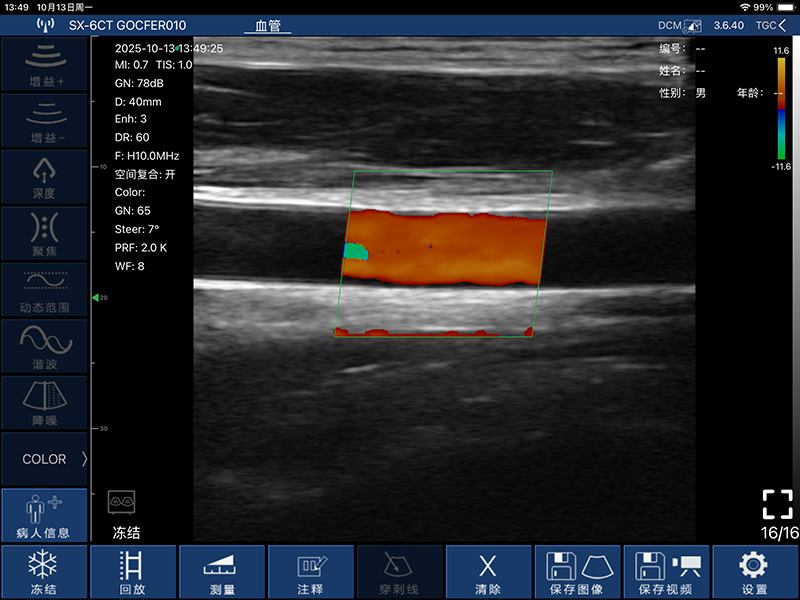

• 频率:凸阵探头3.2MHz/5.0MHz,阵探头7.5MHz/10.0MHz,相控阵探头2.5MHz/5.0MHz

• 深度:凸阵探头90/160/220/305mm,线阵探头20/40/60/80mm,相控阵探头90/120/140/160MM

• 显示模式:B、B/M、Color、PDI、PW

血管自动测量功能